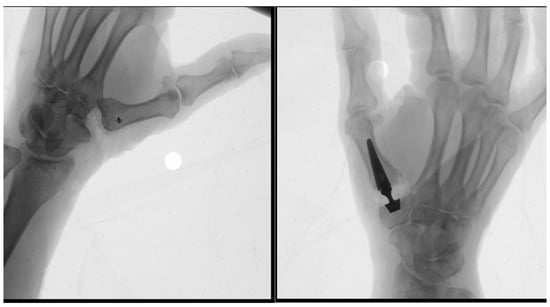

Background: The Orbay approach to volar distal radius described a volar zig-zag incision across the wrist crease, allowing a more distal exposure than traditional approaches. This adaptation enhances mobilization of the proximal radial fragment and improves visualization of both the articular surface and

Background: The Orbay approach to volar distal radius described a volar zig-zag incision across the wrist crease, allowing a more distal exposure than traditional approaches. This adaptation enhances mobilization of the proximal radial fragment and improves visualization of both the articular surface and dorsally displaced distal radius fractures. Methods: In the present paper, we propose a further modification of the volar zig-zag approach, positioning the apex of the incision at the level of the radial styloid. Results: This modification aims to improve visualization of the radial styloid, the articular comminution, and the dorsal aspect of the distal radius, thereby optimizing fracture exposure and reduction. Conclusions: The principal advantage lies in the reduced need for traction along the radial margin of the incision to achieve adequate visualization and the avoidance of crossing the wrist crease, thereby preventing the formation of unsightly or adherent scars.

(This article belongs to the Section Hand Surgery and Research)